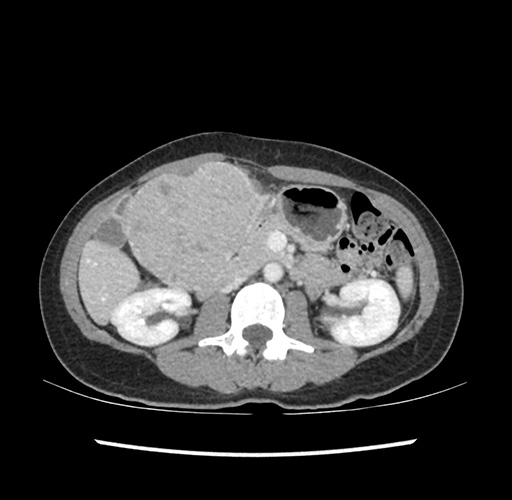

Imaging Analysis

Look through the patient's CT scan to identify any areas of concern for the necessary procedure.

Based on your CT findings, which issue(s) would give reason for "planned slowing down moment(s)" in this case?

Considering a standard left lateral sectionectomy procedure, what step(s) of the operation would you do differently in this case ?